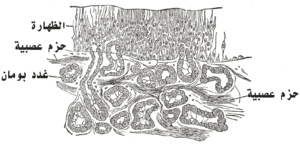

بطانة جوف الأنف

يقسم جوف الأنف بناء على نوع بطانته إلى ثلاثة أقسام:

دهليز الأنف

دهليز الأنف هو المنطقة الأمامية من جوف الأنف ويكون مبطناً بظهارة مماثلة لظهارة الجلد وهي ظهارة رصفية مطبقة متقرنة. تحتوي ظهارة الدهليز على أشعار قصيرة لها دور بتصفية الهواء من الجزيئات الكبيرة التي يحملها.

المنطقة الشمية

يحتوي جوف الأنف على مخاطية شمية تتوضع على المحارة العلوية والثلث العلوي من الحاجز الأنفي. تعصَّب هذه المخاطية بواسطة ألياف العصب الشمي.

المنطقة التنفسية

هي أكبر مناطق الجوف الأنفي وتكون مبطنة بمخاطية تنفسية تحتوي ظهارتها على خلايا مهدبة بينها خلايا كأسية تفرز المخاط. تتمادى هذه المخاطية مع مخاطية البلعوم الأنفي والجيوب جانب الأنفية والقناة الأنفية الدمعية.[1][4]